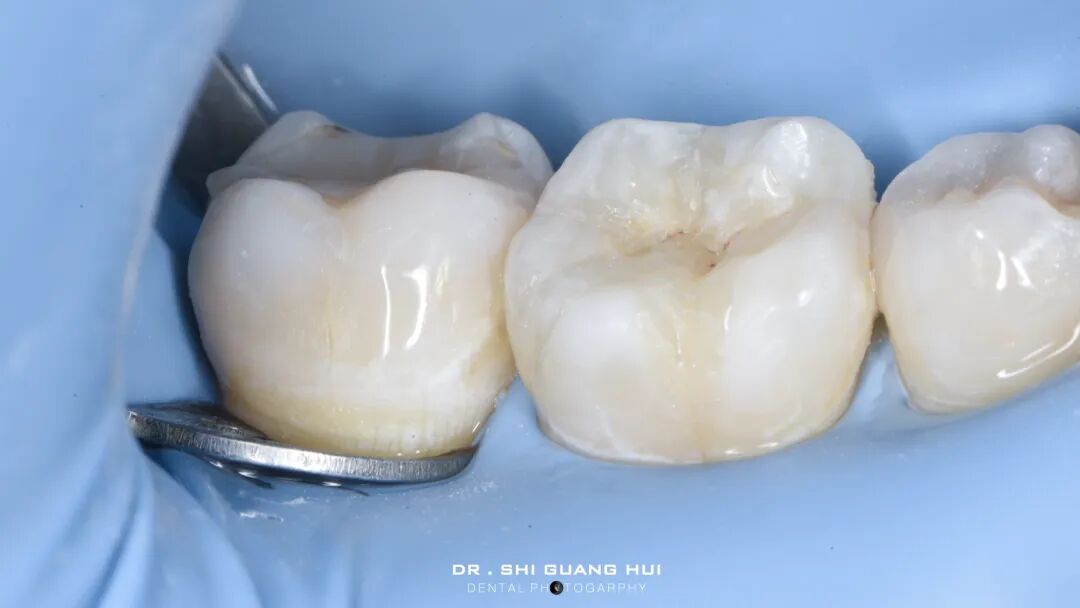

粘接后口内即刻。

咬合检测

口内颊侧观